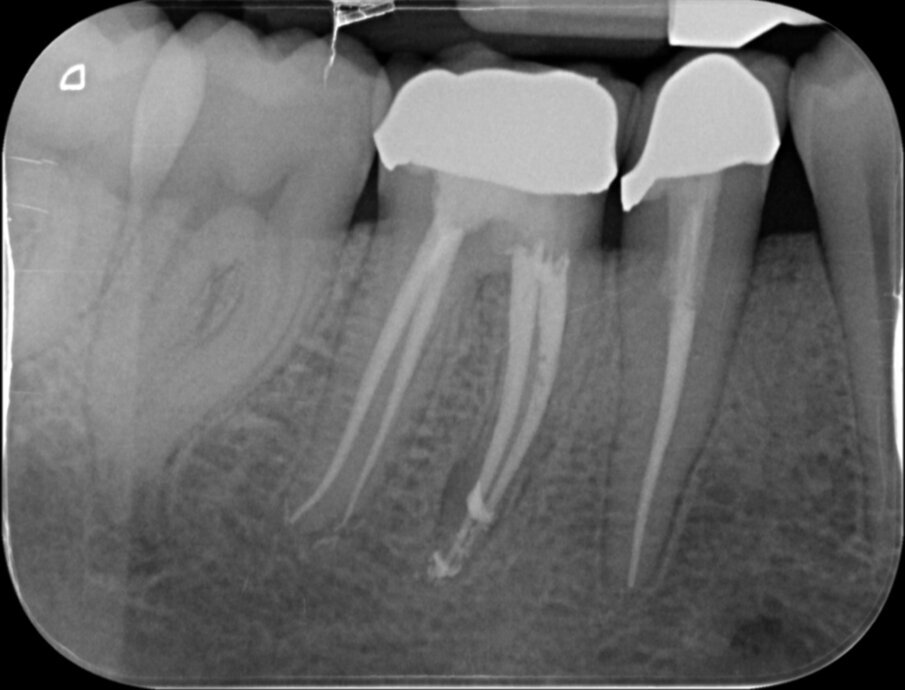

De eindfoto’s stemmen tot optimisme. Röntgenologisch lijkt voldaan aan al de eisen die Schilder aan de vorm van geprepareerde kanalen stelde.

Er lijkt sprake van een gevuld systeem (afbeelding 3 en 4). De puffs in de laatste paar millimeter hebben geen klinische betekenis, maar zijn een normaal bijverschijnsel bij het obtureren van kanalen met een hydraulische obturatiemethode, gebruik makend van warme guttapercha. Hier kozen we voor Thermafil, wat een uitstekende reputatie heeft en de preferente vulmethode is van veel eminente clinici, zoals Buchanan en Ruddle. Vol vertrouwen presenteren we de resultaten aan de patiënt en we schrijven een brief aan de verwijzend tandarts dat het vervaardigen van een kroon nu kan geschieden zonder onaanvaardbare risico’s.

Vier jaar later bezoekt de patiënt wederom op verwijzing onze praktijk. Hij ondervindt wat ongemak van element 46 waar de tandarts 3 jaar geleden een kroon op heeft gemaakt. Bij kauwen is het element iets pijnlijk, iets wat hem sinds twee maanden opgevallen is. Afbeelding 5, 6 en 7 kunnen bevestigen wat de oorzaak is: Een opspelende laesie van endodontische origine (LEO) aan de mesio-buccale radix. Bittere teleurstelling aan onze zijde en een verdrietige patiënt.